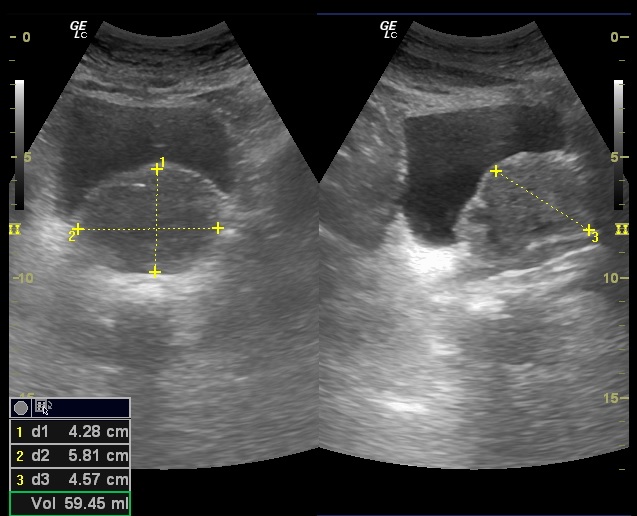

Hallazgos ecográficos

Glándula prostática de 4,28 x 5,81 x 4,57 cm (Figura 1). Volumen prostático: 59,45 ml. Pared de vejiga no engrosada. Se objetiva divertículo vesical (Figura 2) único localizado en pared postero lateral. No se observan lesiones intravesicales ni tampoco en la luz del divertículo (Figura 3). Volumen posmiccional 240 cc.